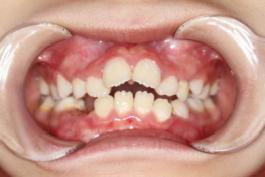

❶ 个别前牙反牙合:此类错牙合可使下颌前伸运动受限。

前

后

❷ 前牙反牙合:此类错牙合影响下颌前伸,影响上颌发育。